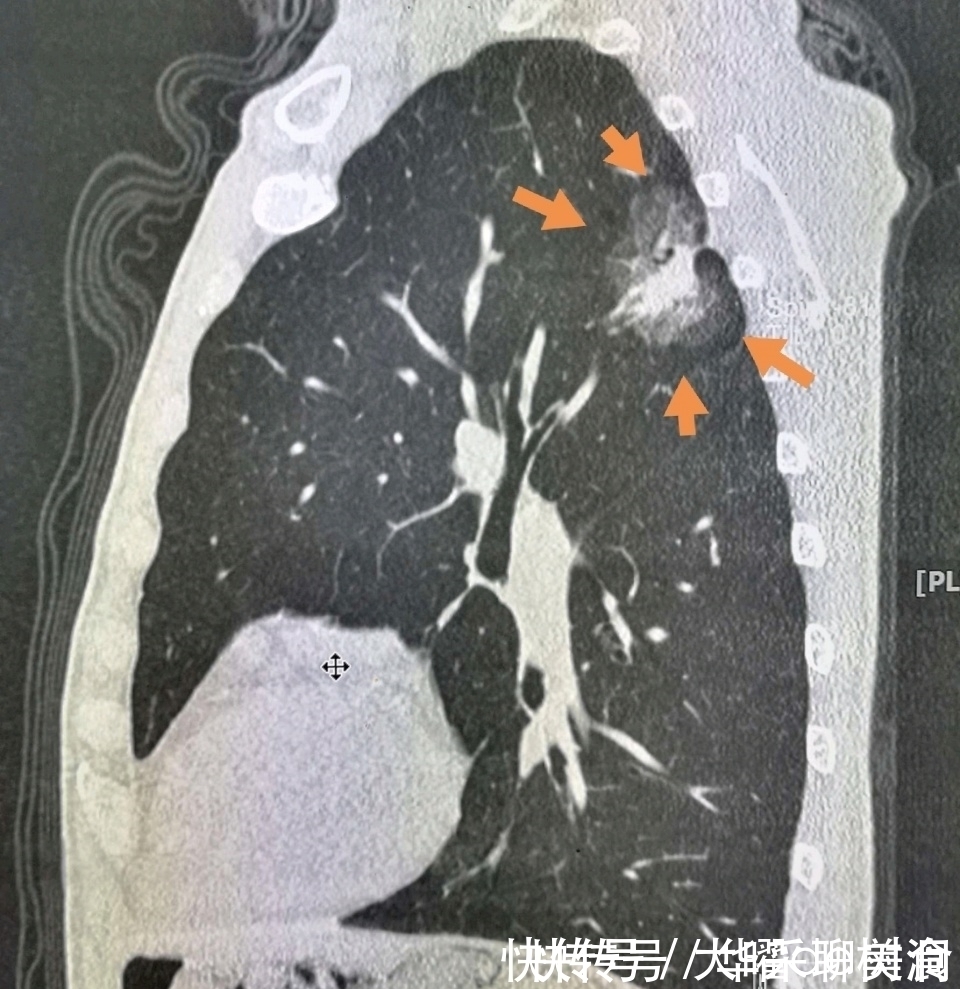

结果一年以后,病灶长大了:

文章插图

并且发生了淋巴结转移,不能手术了。

不幸中的庆幸,是现在晚期肺癌也有很多治疗手段,比如化疗、放疗、射频消融术、靶向药物治疗等,可以延长生命。

这位老太太经过一年治疗之后,病灶明显缩小了:

晚期肺癌病人生存4、5年以上的有很多,今年遇到两位生存七年以上的,都是通过化疗配合靶向治疗实现的。